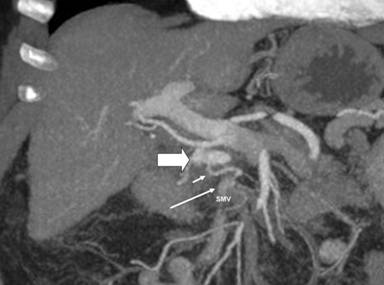

A 75-year-old female performed a quadriphasic abdominal CT examination for the characterization of a focal hepatic lesion, previously identified with a transabdominal ultrasound. Patient had a chronic HCV infection. The physical examination was substantially negative: particularly, the patient did not show any sign or symptom related to the pancreatic arteriovenous malformation or to gastrointestinal bleeding. The MDCT showed a hypervascular area of 3.5x2.5 cm in the pancreatic head, constituted of ectasic vessels (Figure 1); no calcifications were seen inside the mass. The lesion did not determine mass effect or dilation of the main pancreatic duct. During the arterial phase, there was also an early filling of the portal vein and the proximal portion of the superior mesenteric vein. Para-coronal maximum intensity projection and 3D electronic reconstructions made possible to identify the arterial afferents to the malformation (Figure 2), constituted by small aberrant branches from left gastric artery (Figure 3) and posterior inferior pancreaticoduodenal artery (Figure 4); it was also possible to identify the venous efferent drainage, constitute by the portal vein (Figure 5) and the superior mesenteric vein (Figure 6). Other MDCT findings were: presence of a cirrhotic liver with a solid 3.0x2.5 cm mass in the II segment, hyperdense in the arterial phase with washout during the portal phase, referable to hepatocellular carcinoma; an aberrant replacing right hepatic artery arising from the superior mesenteric artery; and a 1.5 cm solid hypodense lesion in the pancreatic body, with fat density and without contrast enhancement, referable to pancreatic lypomatosis.

Figure 5. Maximum intensity projection paracoronal arterial phase reconstruction shows efferent venous flow (long arrow) from the pancreatic arteriovenous malformation (solid arrow) into the portal vein (asterisk). |

Figure 6. Maximum intensity projection paracoronal arterial phase reconstruction, which shows the venous efferent (short arrow) from the pancreatic arteriovenous malformation (solid arrow) to the superior mesenteric vein (SMV; long arrow). |